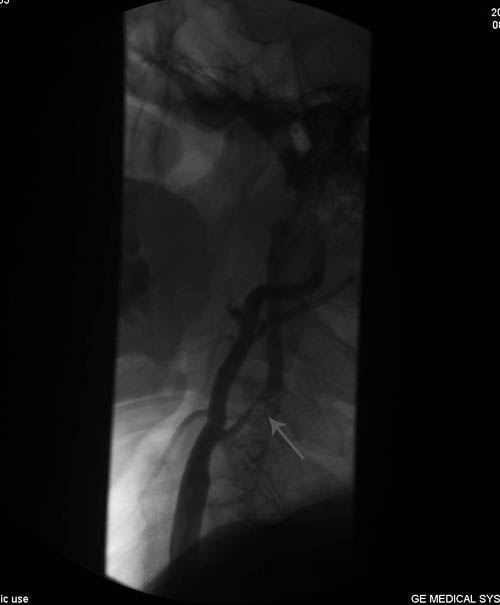

DSA示:右侧颈内动脉起始段重度狭窄。

该患者老年男性,右侧颈内动脉重度狭窄,出现头晕、胸闷症状,有冠心病、脑梗塞、糖尿病病史,CEA手术指征明确。2011年7月21日,协作组张勤奕教授应邀在平顶山市第二人民医院为该患者实施了右侧颈内动脉内膜剥脱术。术后患者恢复良好。